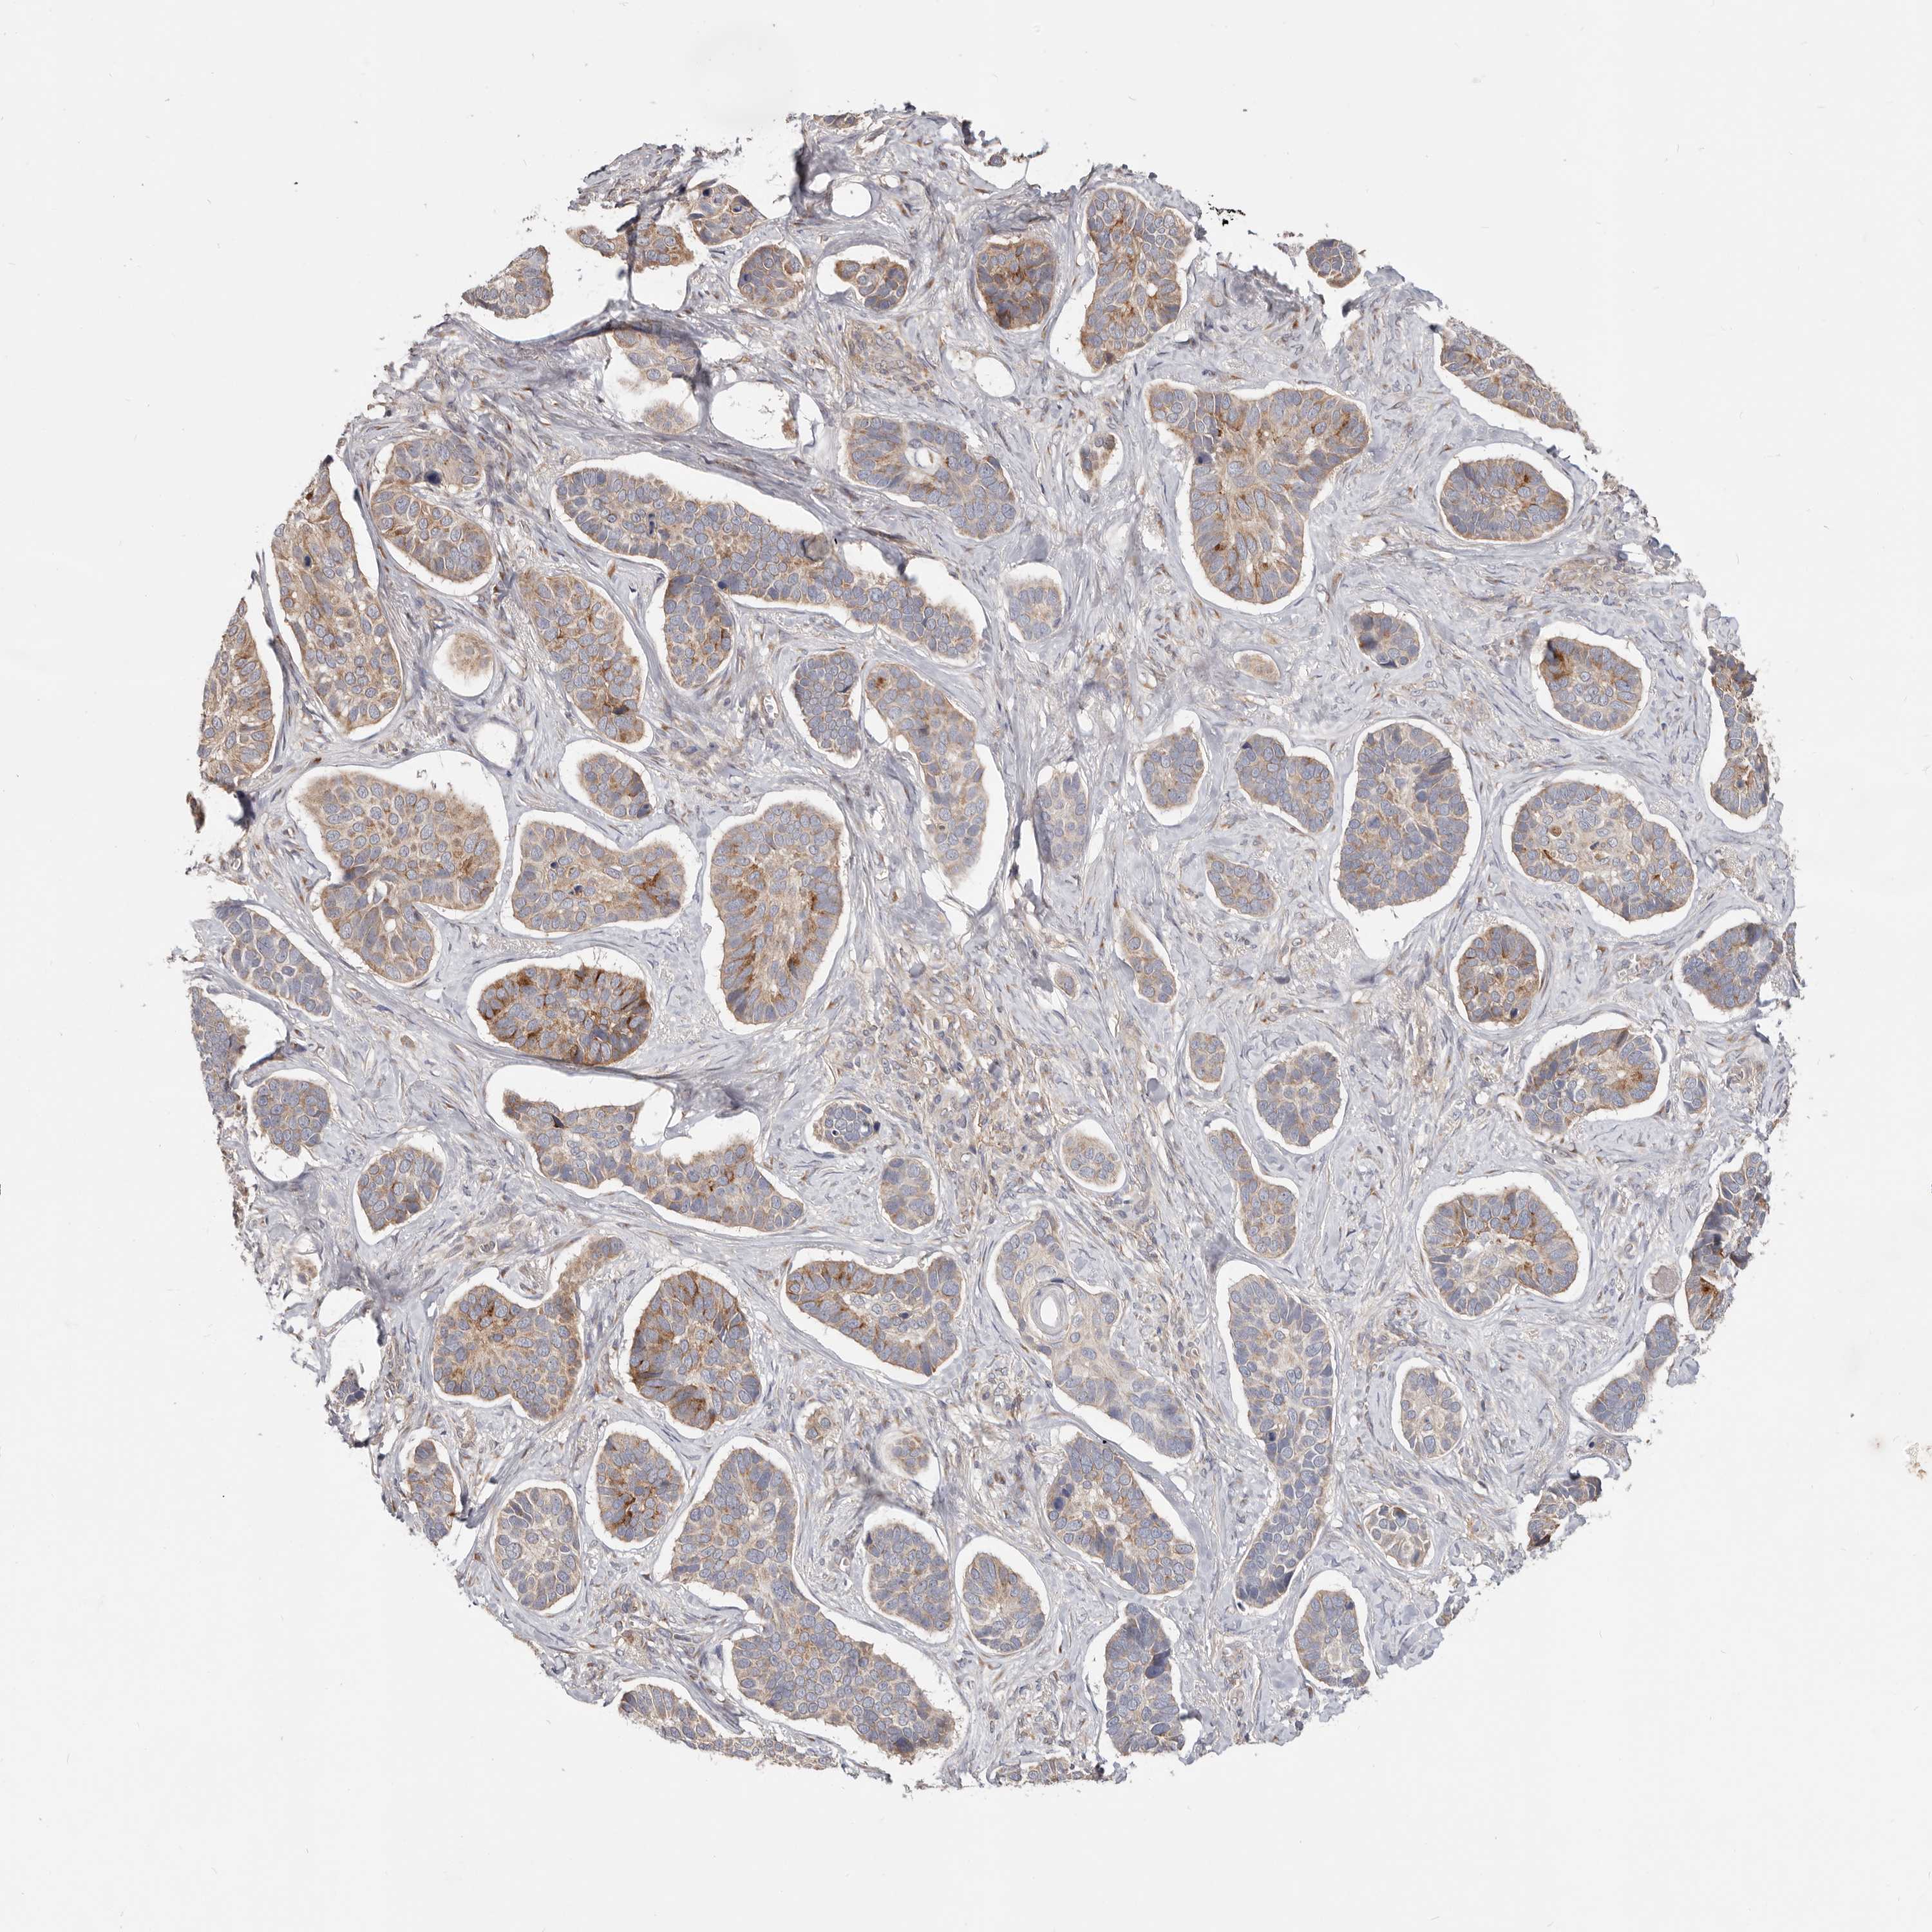

Basal cell and squamous cell cancer

SKIN CANCER - Protein expressioni

A mouse-over function shows sample information and annotation data. Click on an image to view it in a full screen mode. Samples can be filtered based on level of antibody staining by selecting one or several of the following categories: high, medium, low and not detected. The assay and annotation is described here.

Antibody stainingi

Antibody staining in the annotated cell types in the current human tissue is reported as not detected, low, medium, or high, based on conventional immunohistochemistry profiling in selected tissues. This score is based on the combination of the staining intensity and fraction of stained cells.

Each image is clickable and will lead to virtual microscopy that enables deeper exploration of all samples and also displays staining intensity scores, fraction scores and subcellular localization as well as patient and tissue information for each sample.

Antibody HPA029925

Basal cell carcinoma